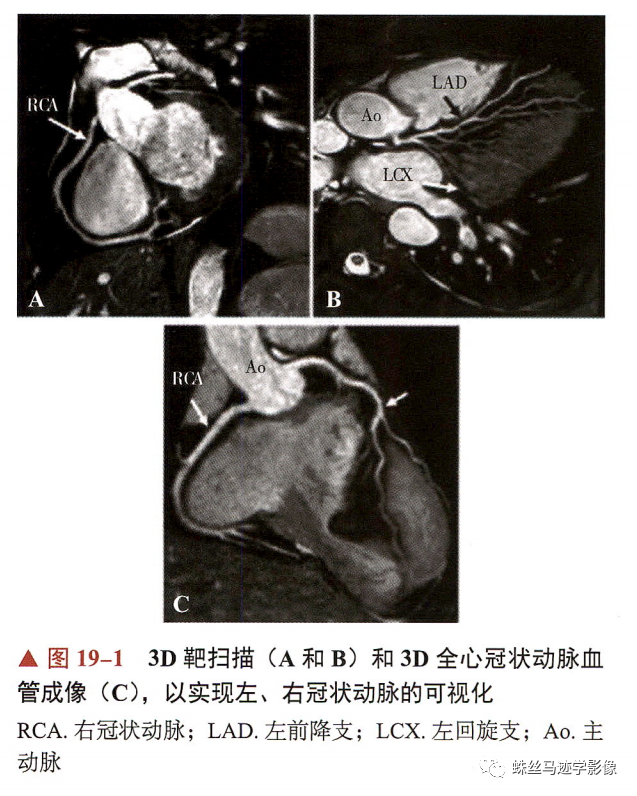

冠状动脉CTCA